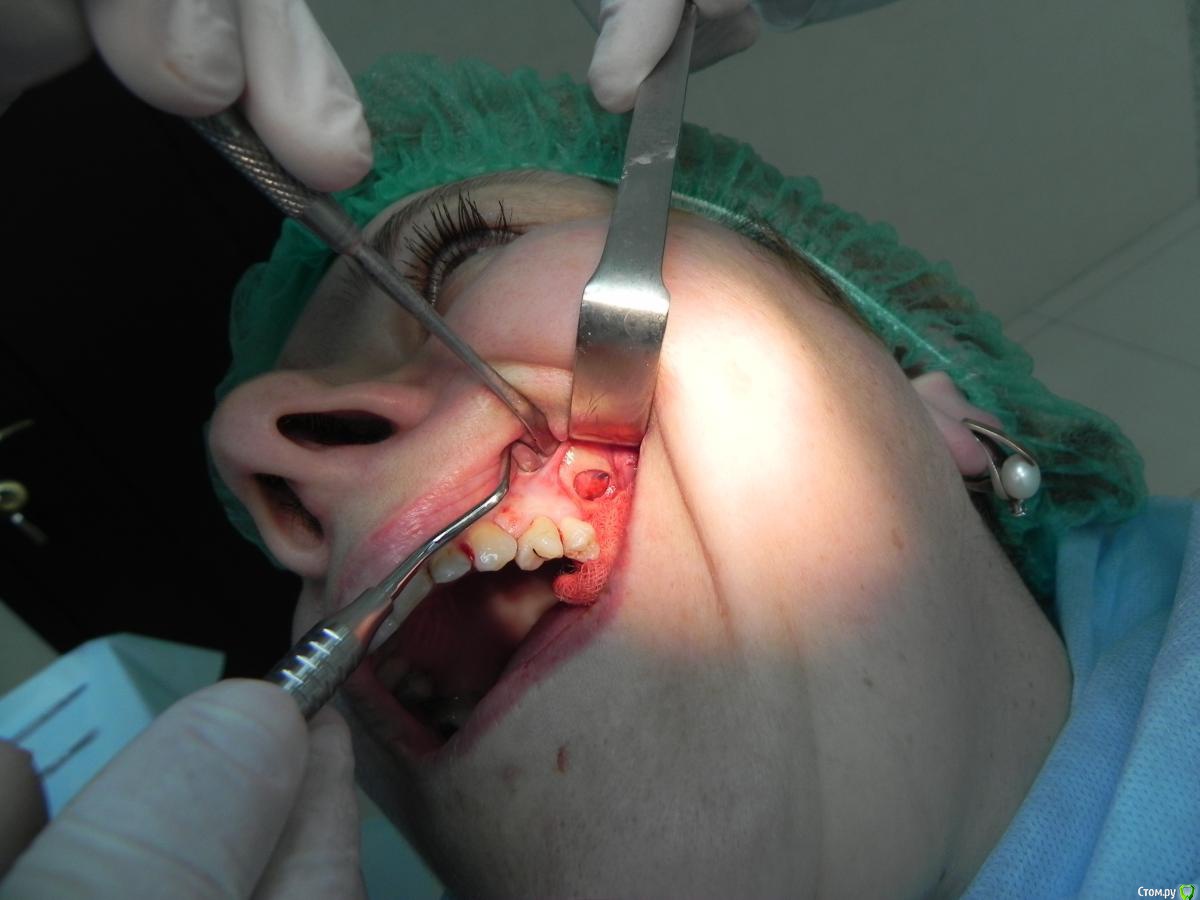

Kostoprav Опубликовано 7 августа, 2015 Поделиться Опубликовано 7 августа, 2015 доступпрепаровка шаровидной костной фрезойпри отслаивании мембраны образовалась маленькая перфа перфорацию" проклеил" коллагеновой мембранойпод мембрану внесен материалмембрана на окноготово может кому из начинающих этот пост полезен будет 1 Ссылка на комментарий